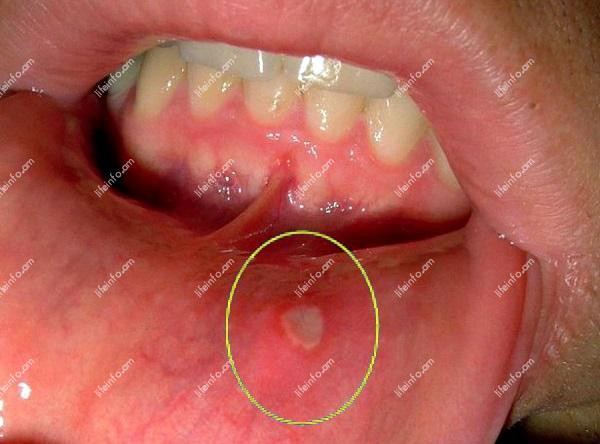

- Ստոմատիտ - բնութագրվում է բերանի խոռոչում մեկ կամ մի քանի խոցերի առաջացմամբ, դրանք ցավոտ են, պատճառում են այրոցի զգացում: Ստոմատիտը առաջացնում է բազմաթիվ բացասական զգացողություններ;

Ստոմատիտ

Բերանի խոռոչի բորբոքային գործընթաց է: Գլխավոր առաջացման պատճառ է համարվում բերանի պատշաճ բանավոր հիգիենայի բացակայությունը: Բայց հիգիենան միակ պատճառը չէ: Առանձնացնում են նաև հետևյալները.

Ախտանիշները հետևյալն են.

- բերանում հայտնվում են վերքեր (խոցեր):

Կարևոր է. շատերը ուշադրություն չեն դարձնում բերանում առաջացող մանր վերքերին: Դա անթույլատրելի է և կարող է հանգեցնել այնպիսի բարդությունների, ինչպիսիք են լնդերի արյունահոսությունը, ատամների ընկնելը և անգամ լարինգիտը:

- քրոնիկ կրկնվող աֆթոզ ստոմատիտ - Այս հիվանդությանը բնորոշ է մի քանի կամ մեծ քանակությամբ խոցերի առաջացումը: Դրանք ունեն սպիտակ փառ, ցավոտ են։ Նաև բնորոշ է հիվանդության կրկնումը: